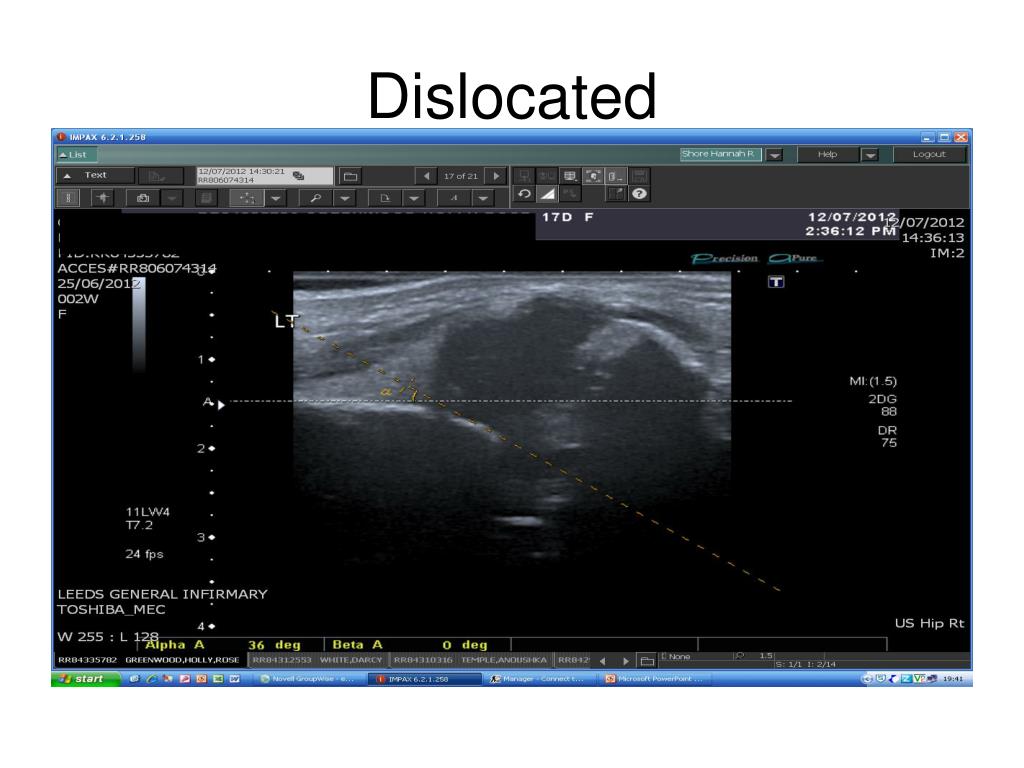

42. Dislocated

43. Types of problems • Dysplastic • Low dislocation • High dislocation

40. Alpha angle Acetabular roof Ileum